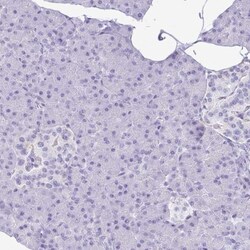

Hydrogen Potassium ATPase Beta Antibody, Novus Biologicals™

Hydrogen Potassium ATPase Beta Polyclonal specifically detects Hydrogen Potassium ATPase Beta in Human samples. It is validated for Immunohistochemistry, Immunohistochemistry-Paraffin.Spot an opportunity for improvement?Share a Content Correction